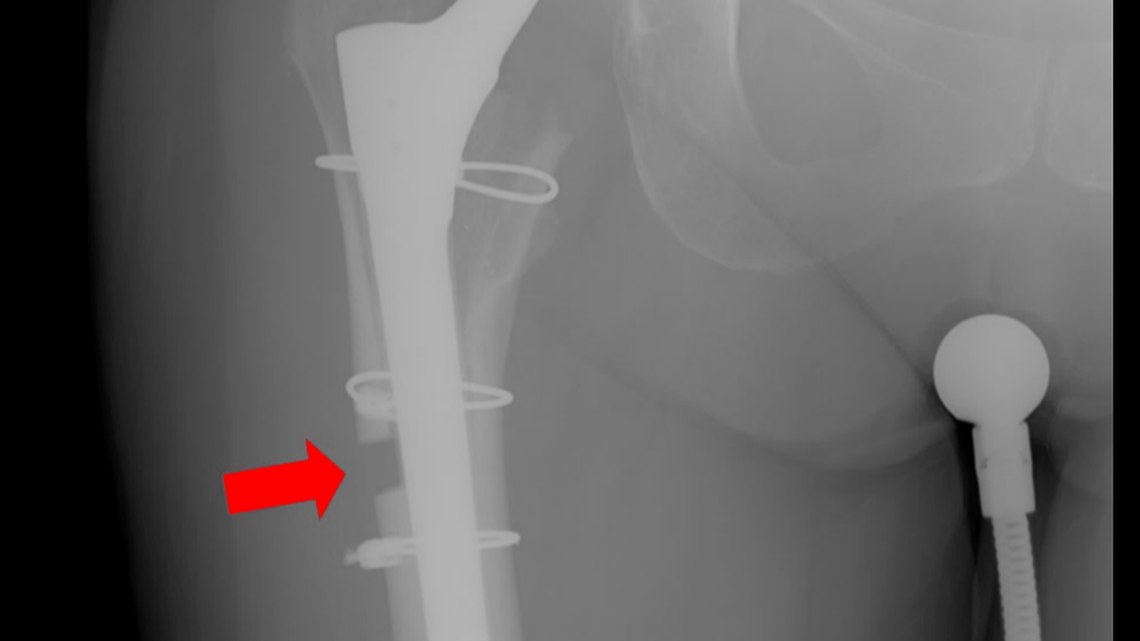

After the woman still reported pain and mobility issues, she received an operation from a different doctor, who she says added a stabilizing implant to the area.

After the woman still reported pain and mobility issues, she received an operation from a different doctor, who she says added a stabilizing implant to the area. Complaint

Shea eventually switched doctors and got another surgery in December 2019 to add a stabilizing piece of hardware on her femur. The x-ray shows the new device and a gap in her femur bone that never healed.